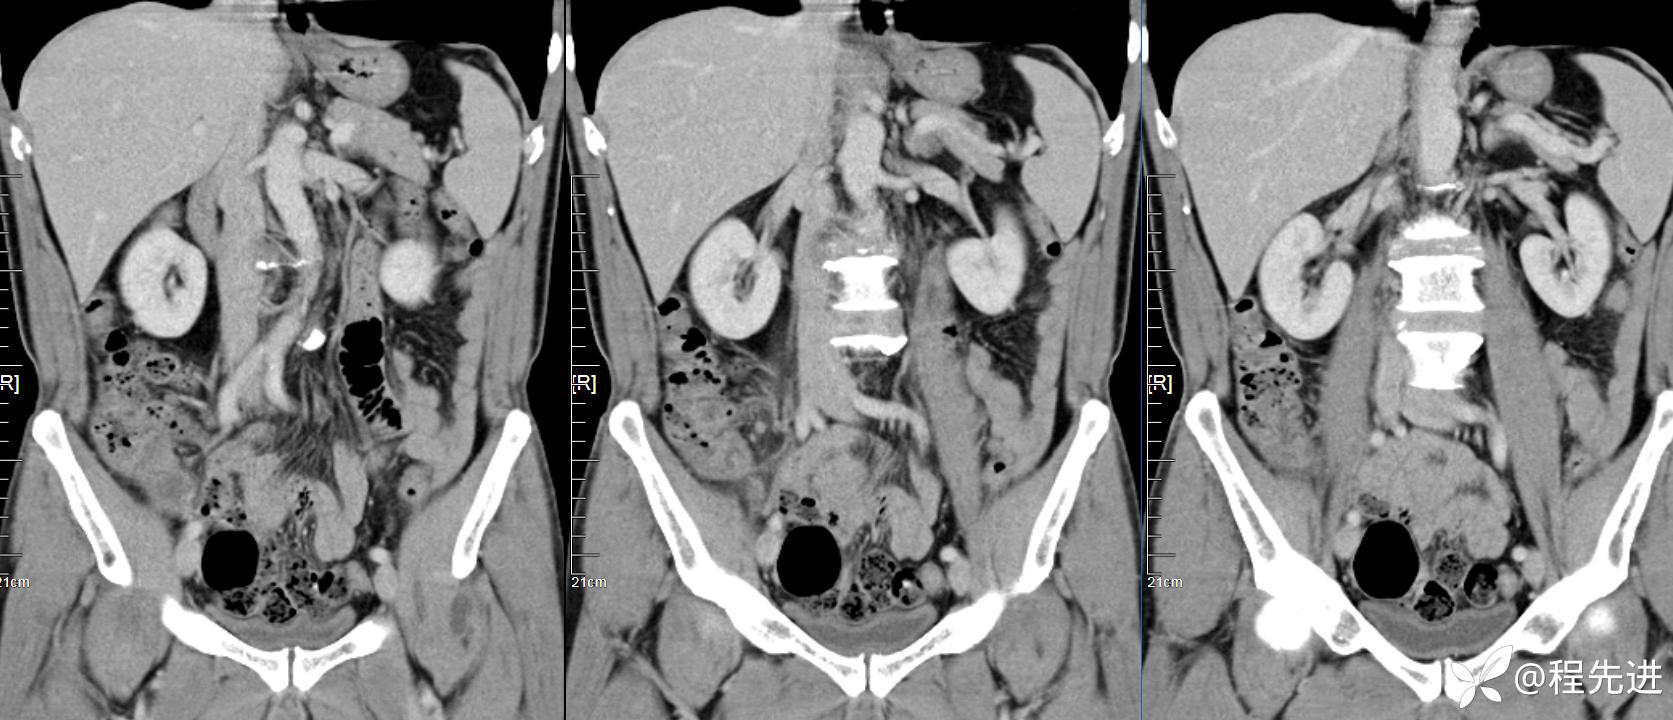

【患者信息】:男,61岁

【现病史及既往史】:右下腹部疼痛伴腹胀2天

【影像检查】